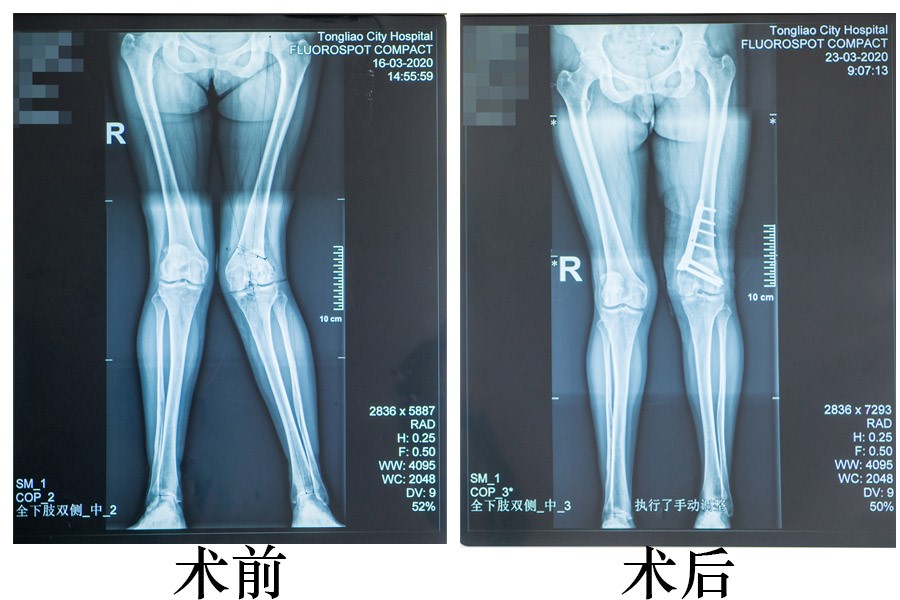

入院后经详细查体,结合影像学检查,显示患者左膝关节畸形严重,外翻角度达到30°。针对患者病情,骨三科兰荫梧主任带领科室的医生们进行了详尽的讨论,在与家属充分沟通及综合考虑患者情况后,决定为其进行双平面闭合截骨术。和开放截骨相比,闭合截骨矫形手术更有利于患者术后截骨处尽快愈合,早期康复;另外,施行双平面截骨,既不损伤髌股关节软骨面,又可以防止股骨截骨后旋转畸形等并发症发生。此手术难点在于术前必须精准计算出截骨度数,确定截骨平面及术中精准操作。术中如果截骨度数过大或不够都将严重影响手术效果,造成手术失败。为了达到精准治疗,最大限度地减少病人的创伤,骨三科手术团队在术前对截骨部位的选取、角度、截骨量等都用电脑做了精心的绘图。在完善的准备后,手术于3月19日在我院西院区完成,由骨三科兰荫梧主任主刀,杨松涛、刘思佳医生协助。手术进展顺利,术后患者复查双下肢全长X光显示:左下肢力线恢复良好,膝外翻得到矫正,手术取得了良好的疗效,患者及家属非常满意。

据兰荫梧主任及杨松涛医生介绍,截骨矫形就是通过改善膝关节的负重力线,使髋、膝、踝关节的中心连线近于1条直线,也就是恢复正常的下肢机械轴线,以达到矫正畸形、确保膝关节力学稳定和解除疼痛的目的。此类股骨截骨矫正手术属于四级手术,是技术难度最高级别的手术,在我市较为少见。